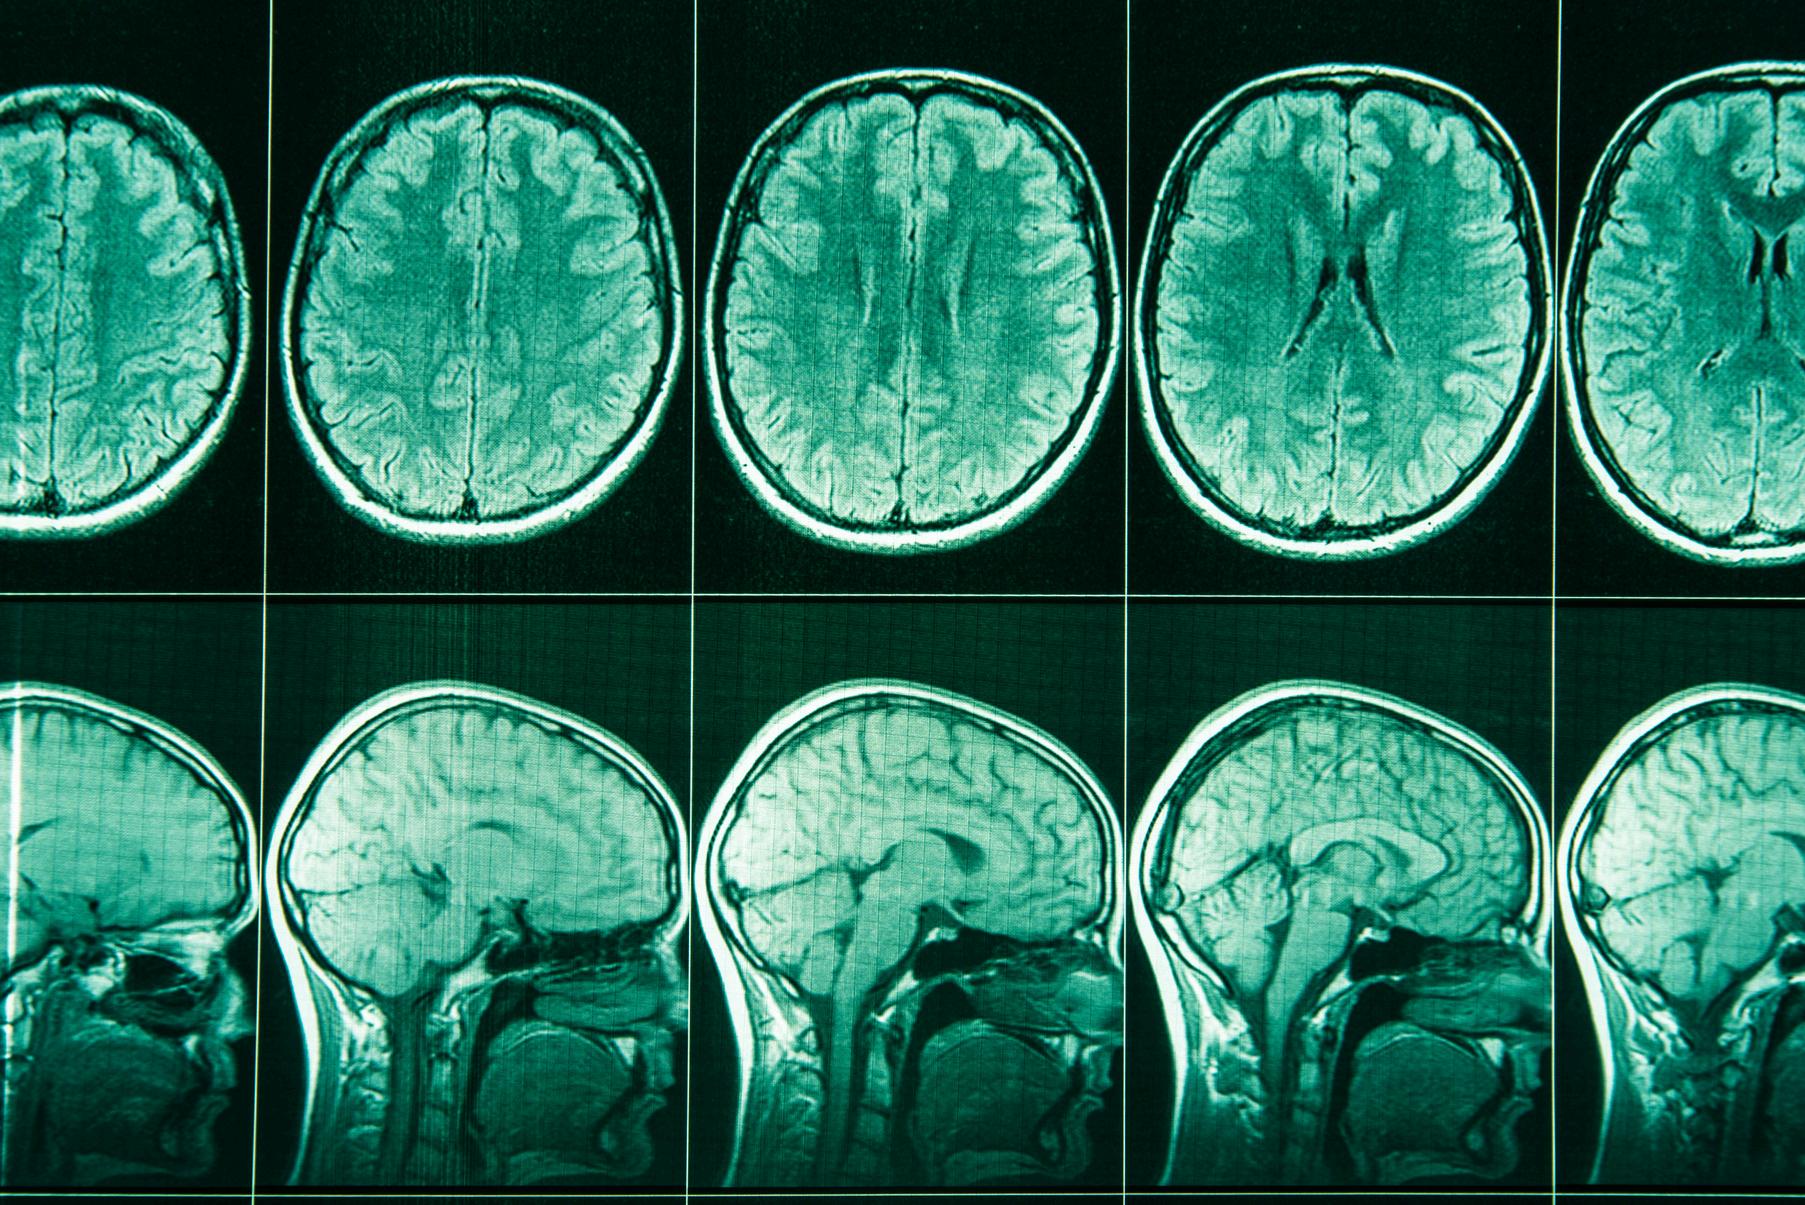

In this unit, students investigate the complex nature of psychological development as well as the role the human brain plays in mental processes and behaviour.

This includes: the interaction between hereditary and environmental factors on a person’s psychological development the process of psychological development (emotional, cognitive and social development) over the lifespan the concepts of normality, neurotypicality and neurodiversity including ADHD and autism spectrum disorder the structure and function of the brain the impact of brain injuries and neurological disorders on an individual’s functioning.